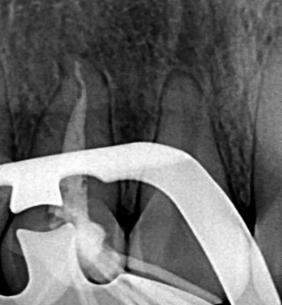

Se solicita una radiografía periapical, en la misma se observa la presencia del conducto radicular único, ancho con una sola cámara pulpar, está misma

ubicada en la corona mesiopalatina, también se puede observar la imagen radiopaca que evidencia la cúspide en garra (Fig.2).

Figura Nº2. Radiografía periapical que muestra que la pieza dentaria presenta una sola raíz y un solo conducto radicular, además presenta la imagen radiopaca de la cúspide en garra.

Fuente: Elaboración propia, septiembre 2021.